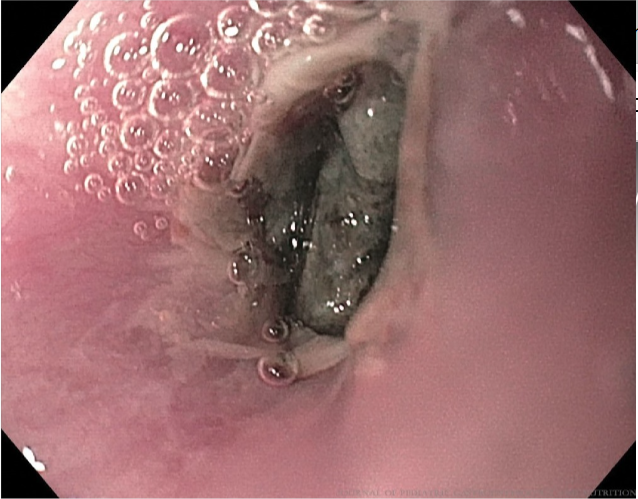

3 yo boy with abd pain and fever for the last 10 days. Abd US shows a dilated CBD and echogenic content. Side viewing endoscopy and cholangiography as shown. What is the next step in management? Answer and learn more 👉 bit.ly/3htf9YP?utm_so… #imageofthemonth #quickpoll

JPGNonline's tweet image. 3 yo boy with abd pain and fever for the last 10 days.  Abd US shows a dilated CBD and echogenic content. Side viewing endoscopy and cholangiography as shown.

What is the next step in management?

Answer and learn more 👉 bit.ly/3htf9YP?utm_so…

#imageofthemonth #quickpoll